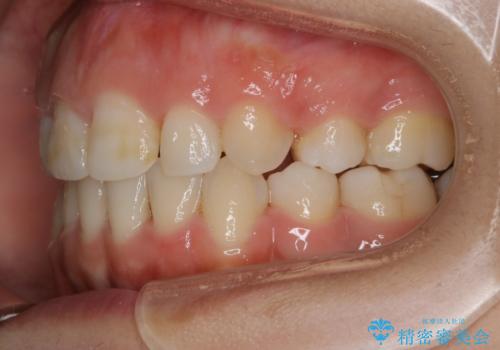

ガタつきの度合いは軽度でしたが歯列の幅が狭く、その分前歯が上下とも前方に出てしまっていました。

しっかりと口元・顔貌まで変化を起こせるように上下左右の第一小臼歯を抜歯し、ワイヤー装置にて矯正を開始することとなりました。